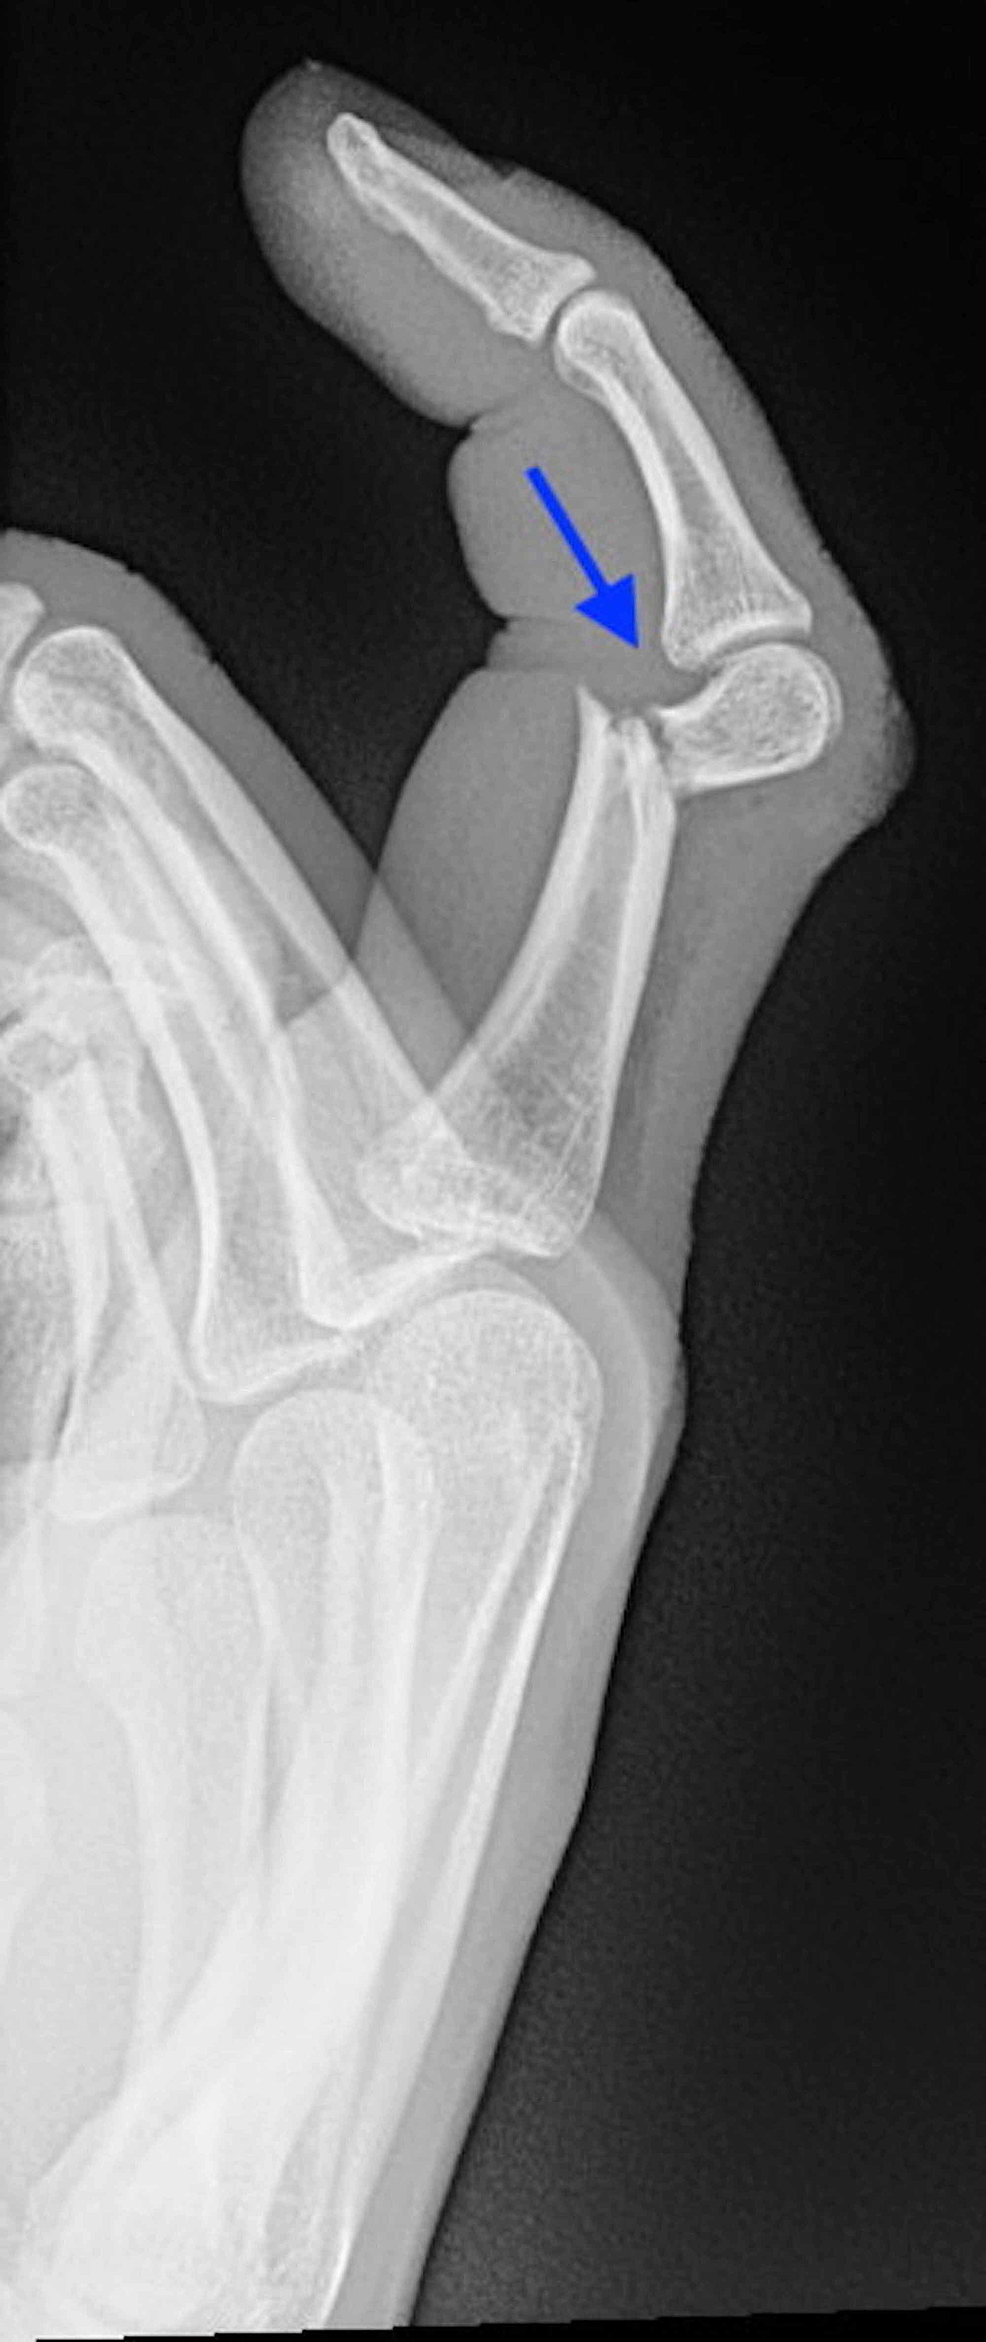

발가락 골절 수술 치료

- 적용 시기: 복합 골절, 압박 골절, 뼈 조각이 여러 개로 나뉜 경우처럼 깁스나 스플린트만으로 회복이 어려운 경우.

- 회복 기간: 수술 후에도 2~4주 이상의 안정기가 필요하며, 이후에는 재활 운동이 필수로 따라옵니다.

- 치료 방식: 핀을 박거나 금속판을 대는 방법을 사용합니다. 골절 부위를 정확히 정렬하고 뼈가 잘못 붙지 않도록 하는 것이 핵심입니다.